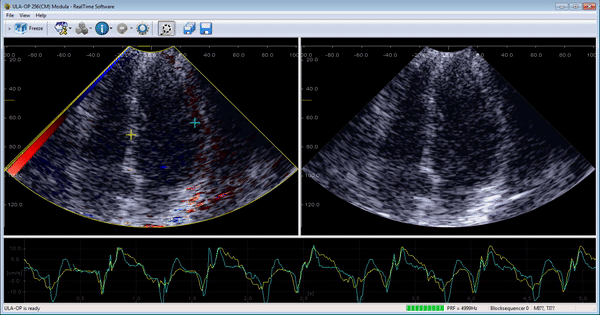

Real-time tissue Doppler imaging of the left ventricle in 4-chamber view